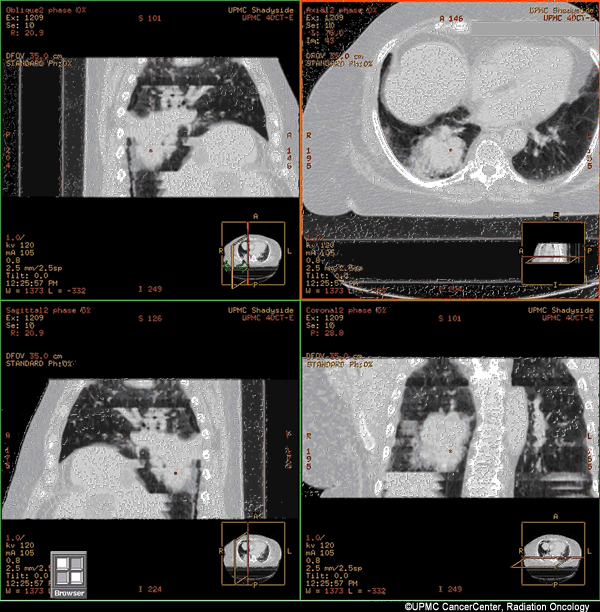

4D CT uses a new technology that captures the location and movement of your tumor and the movement of your body’s organs over time.

This is valuable for accurately treating tumors located on or near organs that move, such as those in the chest and abdomen.

The scanner makes a 4D image showing:

- Your body’s breathing.

- How the tumor moves.

- How movement of nearby organs affects the position of your tumor.